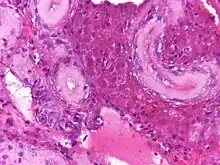

En biopsias realizadas a niños con el síndrome de Klinefelter, se ha observado una disminución en el número de células germinales. No obstante, después de la pubertad se aprecia hialinización y fibrosis de los túbulos seminíferos. Estos cambios histológicos son muy característicos del síndrome, y los cuales originan disminución en el volumen testicular así como aumento de su consistencia. También se observa ausencia de células germinales, hiperplasia y agregación de las células de Leydig, como respuesta a la hiperestimulación por la hormona hormona luteinizante.[23]